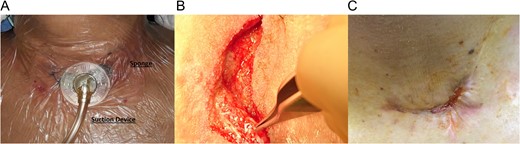

(A) Functional V.A.C. system in-patient. (B) Granulation tissue in the cervical wound. (C) Wound after therapy.

Partial opening of the cervical wound was done, and necrotic tissue debridement with extensive irrigation of the wound with saline and iodine over the cervical esophagus was performed. After this to protect the esophago-colonic anastomosis from direct contact with the V.A.C. a small paraffin gauze dressing (Lomatuell H, Paraffin Gauze Dressing) was placed over the cervical esophagus. The V.A.C. sponge was fashioned to fit the wound and placed over it. The adhesive drape was fixed to the neck skin and continuous suction between 100 and 125 mmHg was installed (Fig. 2A). In the first week, V.A.C. system drained about 50cc of saliva-like fluid daily and was changed every 2 days, once granulation tissue had begun to form over the wound, the system was changed every 5 days and no paraffin gauze was used (Fig. 2B). All V.A.C. changes were done in the operating room and during the first week of V.A.C. treatment, patient received total parental nutrition, on the 10th day patient was able to ingest liquids. Twelve days after initial use, the leak closed, since no fluid came out of the V.A.C. system, and after the patient resumed full normal diet, she was discharged home. On follow-up controls, the patient was in good condition (Fig. 2C).